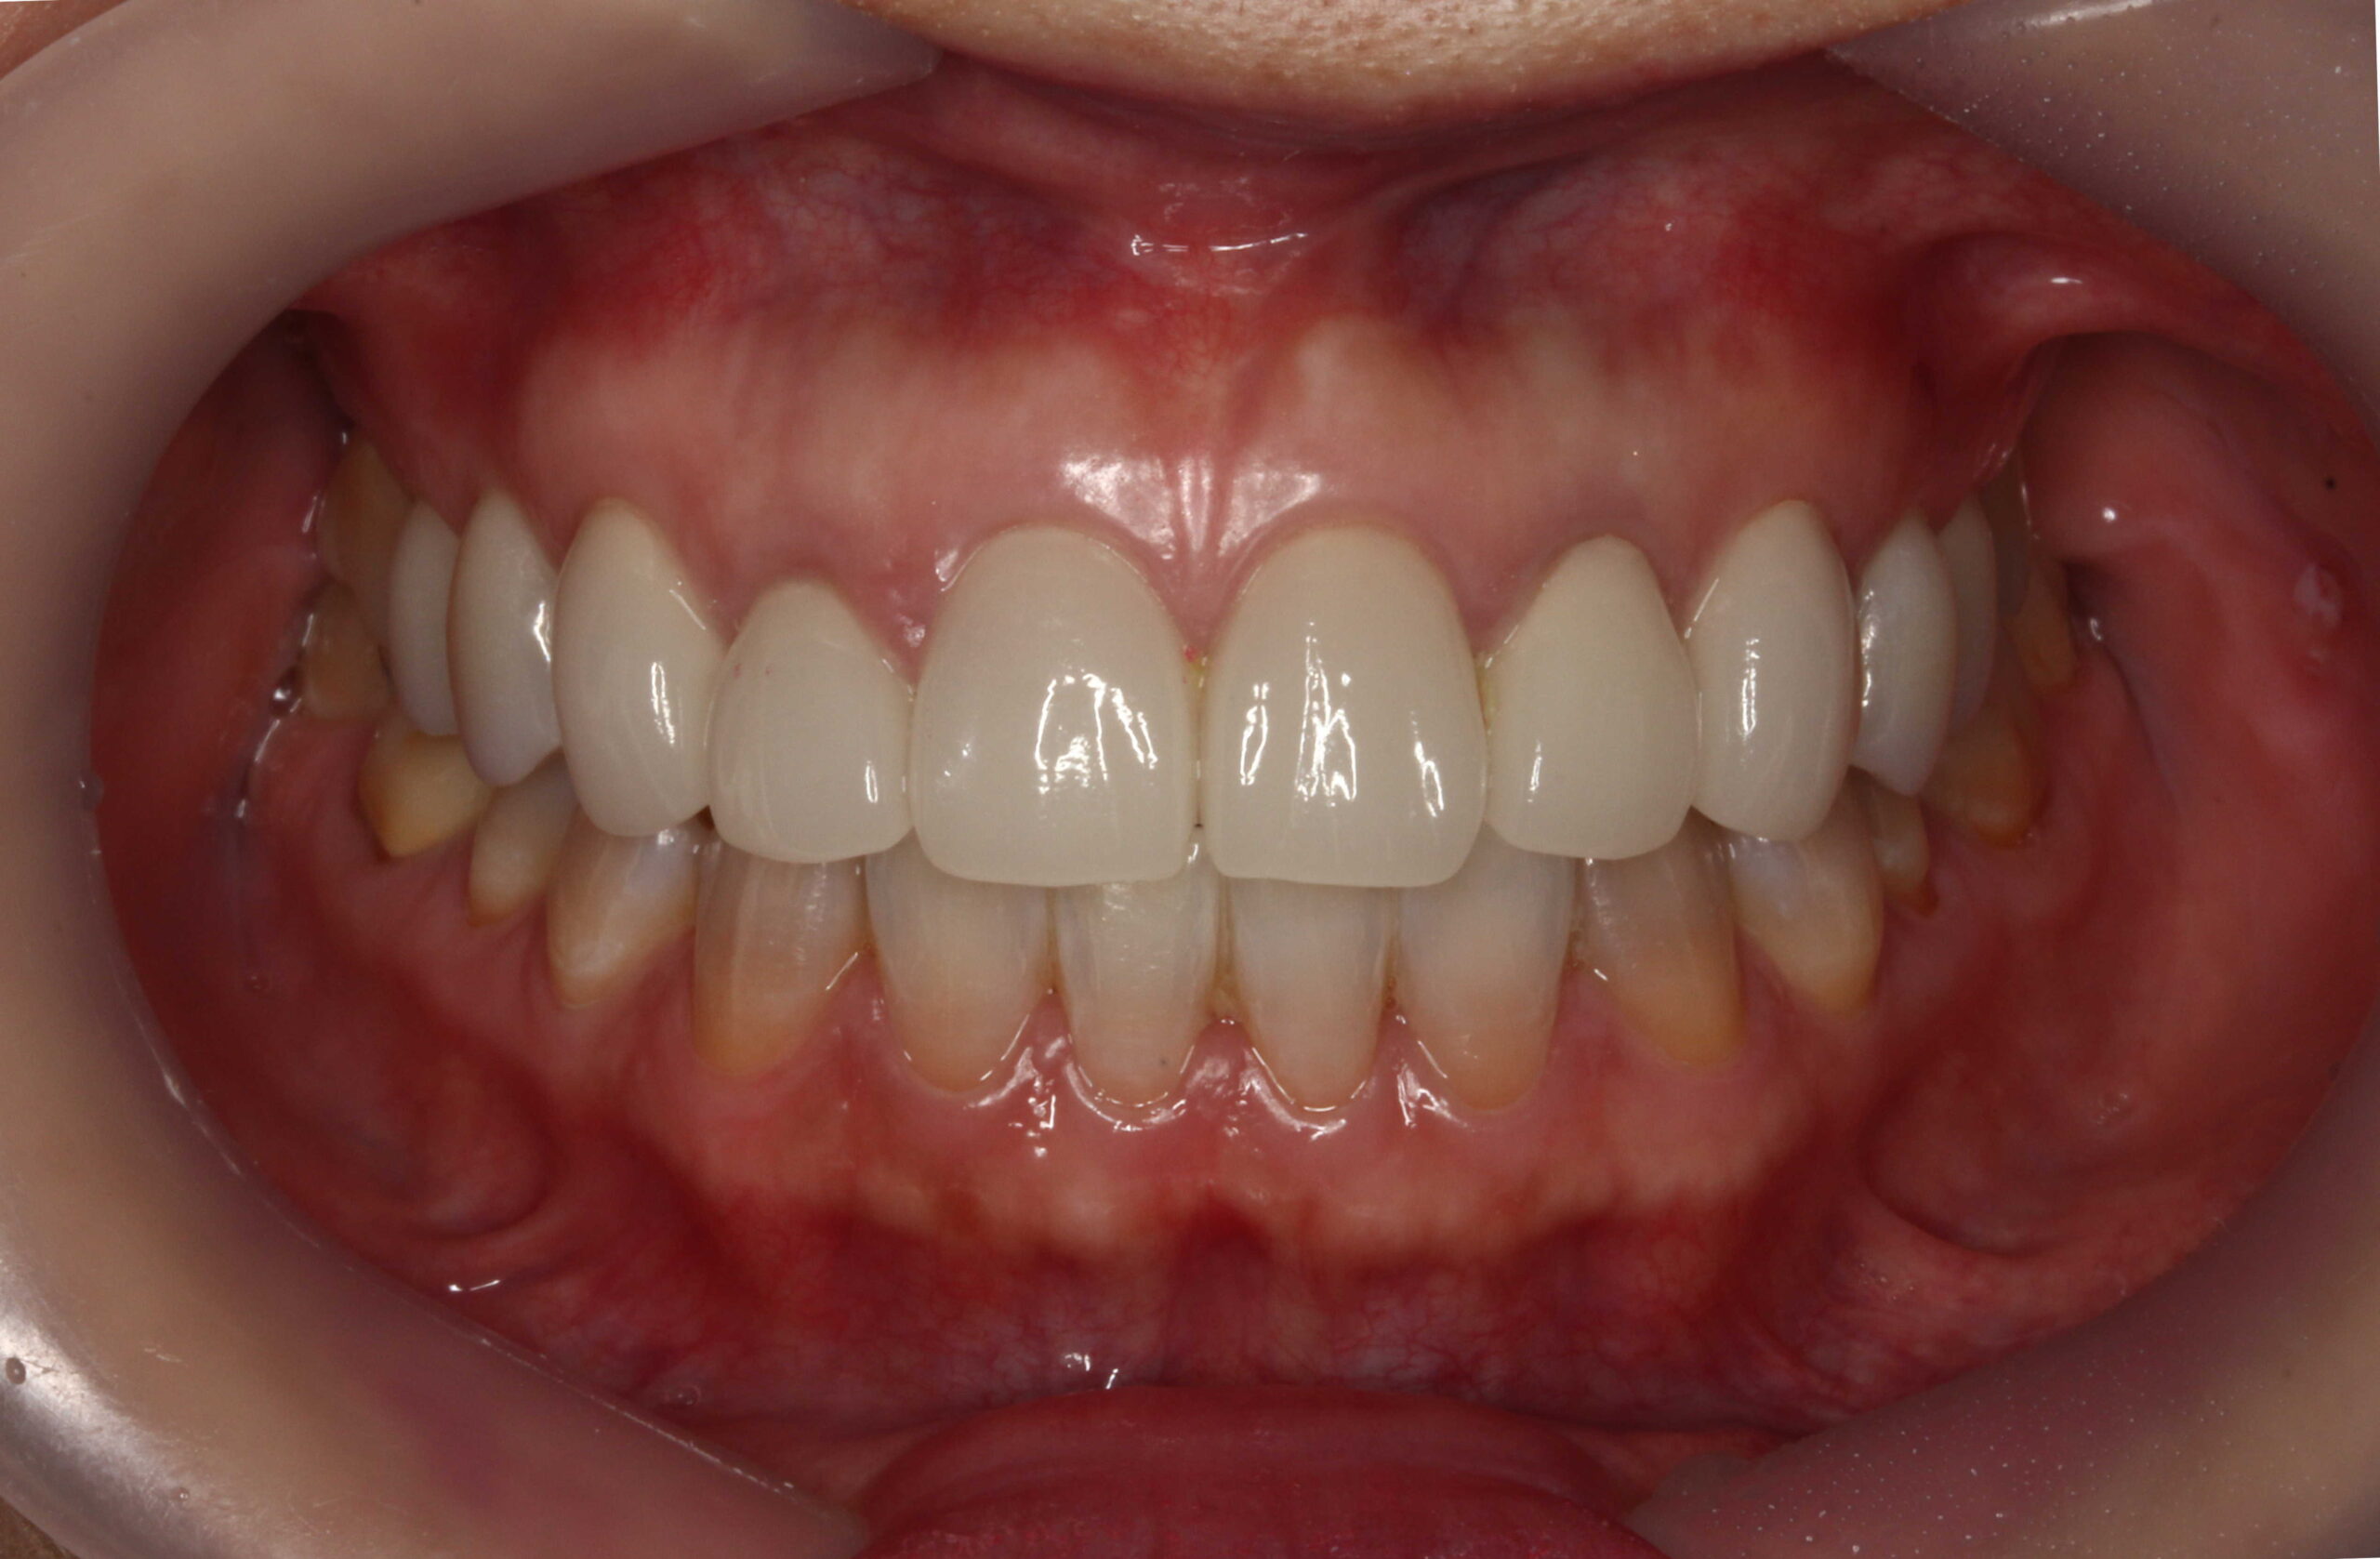

術前 削らないラミネートベニア4本

+クラウン2本

全体的にはホワイトニングを行っています。

テトラサイクリン歯 と 左上2や右下1などの失活歯 にもホワイトニング効果は出ています。

削らないラミネートベニアは極薄のセラミックベニアなので透明感があるので元の歯の色味が透けます。(透過性のないベニアも製作出来ますが、透明感がないので色味が白浮きして不自然になります。)

上の前歯(右上32と左上23) にも、削らないラミネートベニアの前にホワイトニングを行っています。

従来の方法であれば、上前歯6本をラミネートベニアやセラミッククラウンを行うために削って、セラミック材料を被せる方法で行っていました。